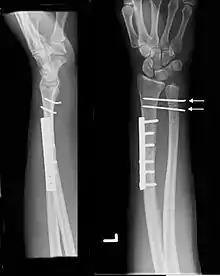

![]() | |

| Galeazzi fracture. Arrow points at the dislocated ulnar head | |